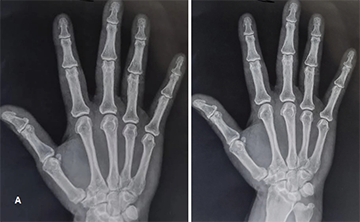

Last year, Scientific Reports retracted a paper comparing the condition, which the authors dubbed Middle East Pain Syndrome, to rheumatoid arthritis for failing to establish a clear distinction between the two ailments. The new article, published in January 2025 in BMC Rheumatology with two overlapping authors, compares MEPS to fibromyalgia, claiming it is distinct for its "hand tufts spur-like excrescences".